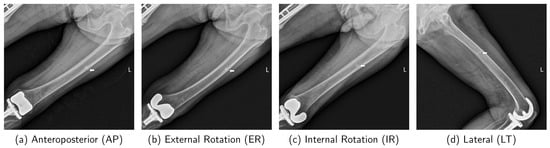

The University Hospital (UH) dataset was collected at Kyungpook National University Hospital (KNUH) between August 2010 and November 2022. It comprises 794 X-ray images from 236 patients, including 430 images from 92 patients with IAFF and 364 images from 144 patients in the normal group. The IAFF cases are further categorized into D-IAFF and S-IAFF, and three orthopedic specialists reviewed and classified the data into normal or IAFF types. The dataset comprises images of both the left and right femurs, obtained from different radiographic views, including Anteroposterior (AP), External Rotation (ER), Internal Rotation (IR), and Lateral (LT). To ensure data independence for each patient, reflecting real clinical settings, the training and evaluation sets are split by patient. Among the 794 collected images, 666 images (IAFF: 354, Normal: 312) were randomly selected for 5-fold cross-validation training, and the remaining 128 images (IAFF: 76, Normal: 52) were used for evaluation. This dataset was approved by the KNUH Institutional Review Board under approval number KNUH202402007-HE001 on 26 February 2024.

4.9. Analysis of Classification Performance and Robustness Across Different X-Ray Radiographic Views